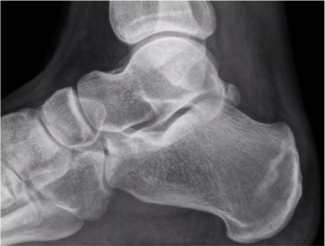

With the goal of getting patients back to activity, this author focuses on conservative treatment for ankle sprains, taking a closer look at isolated inversion sprains, high ankle sprains, and deltoid sprains.